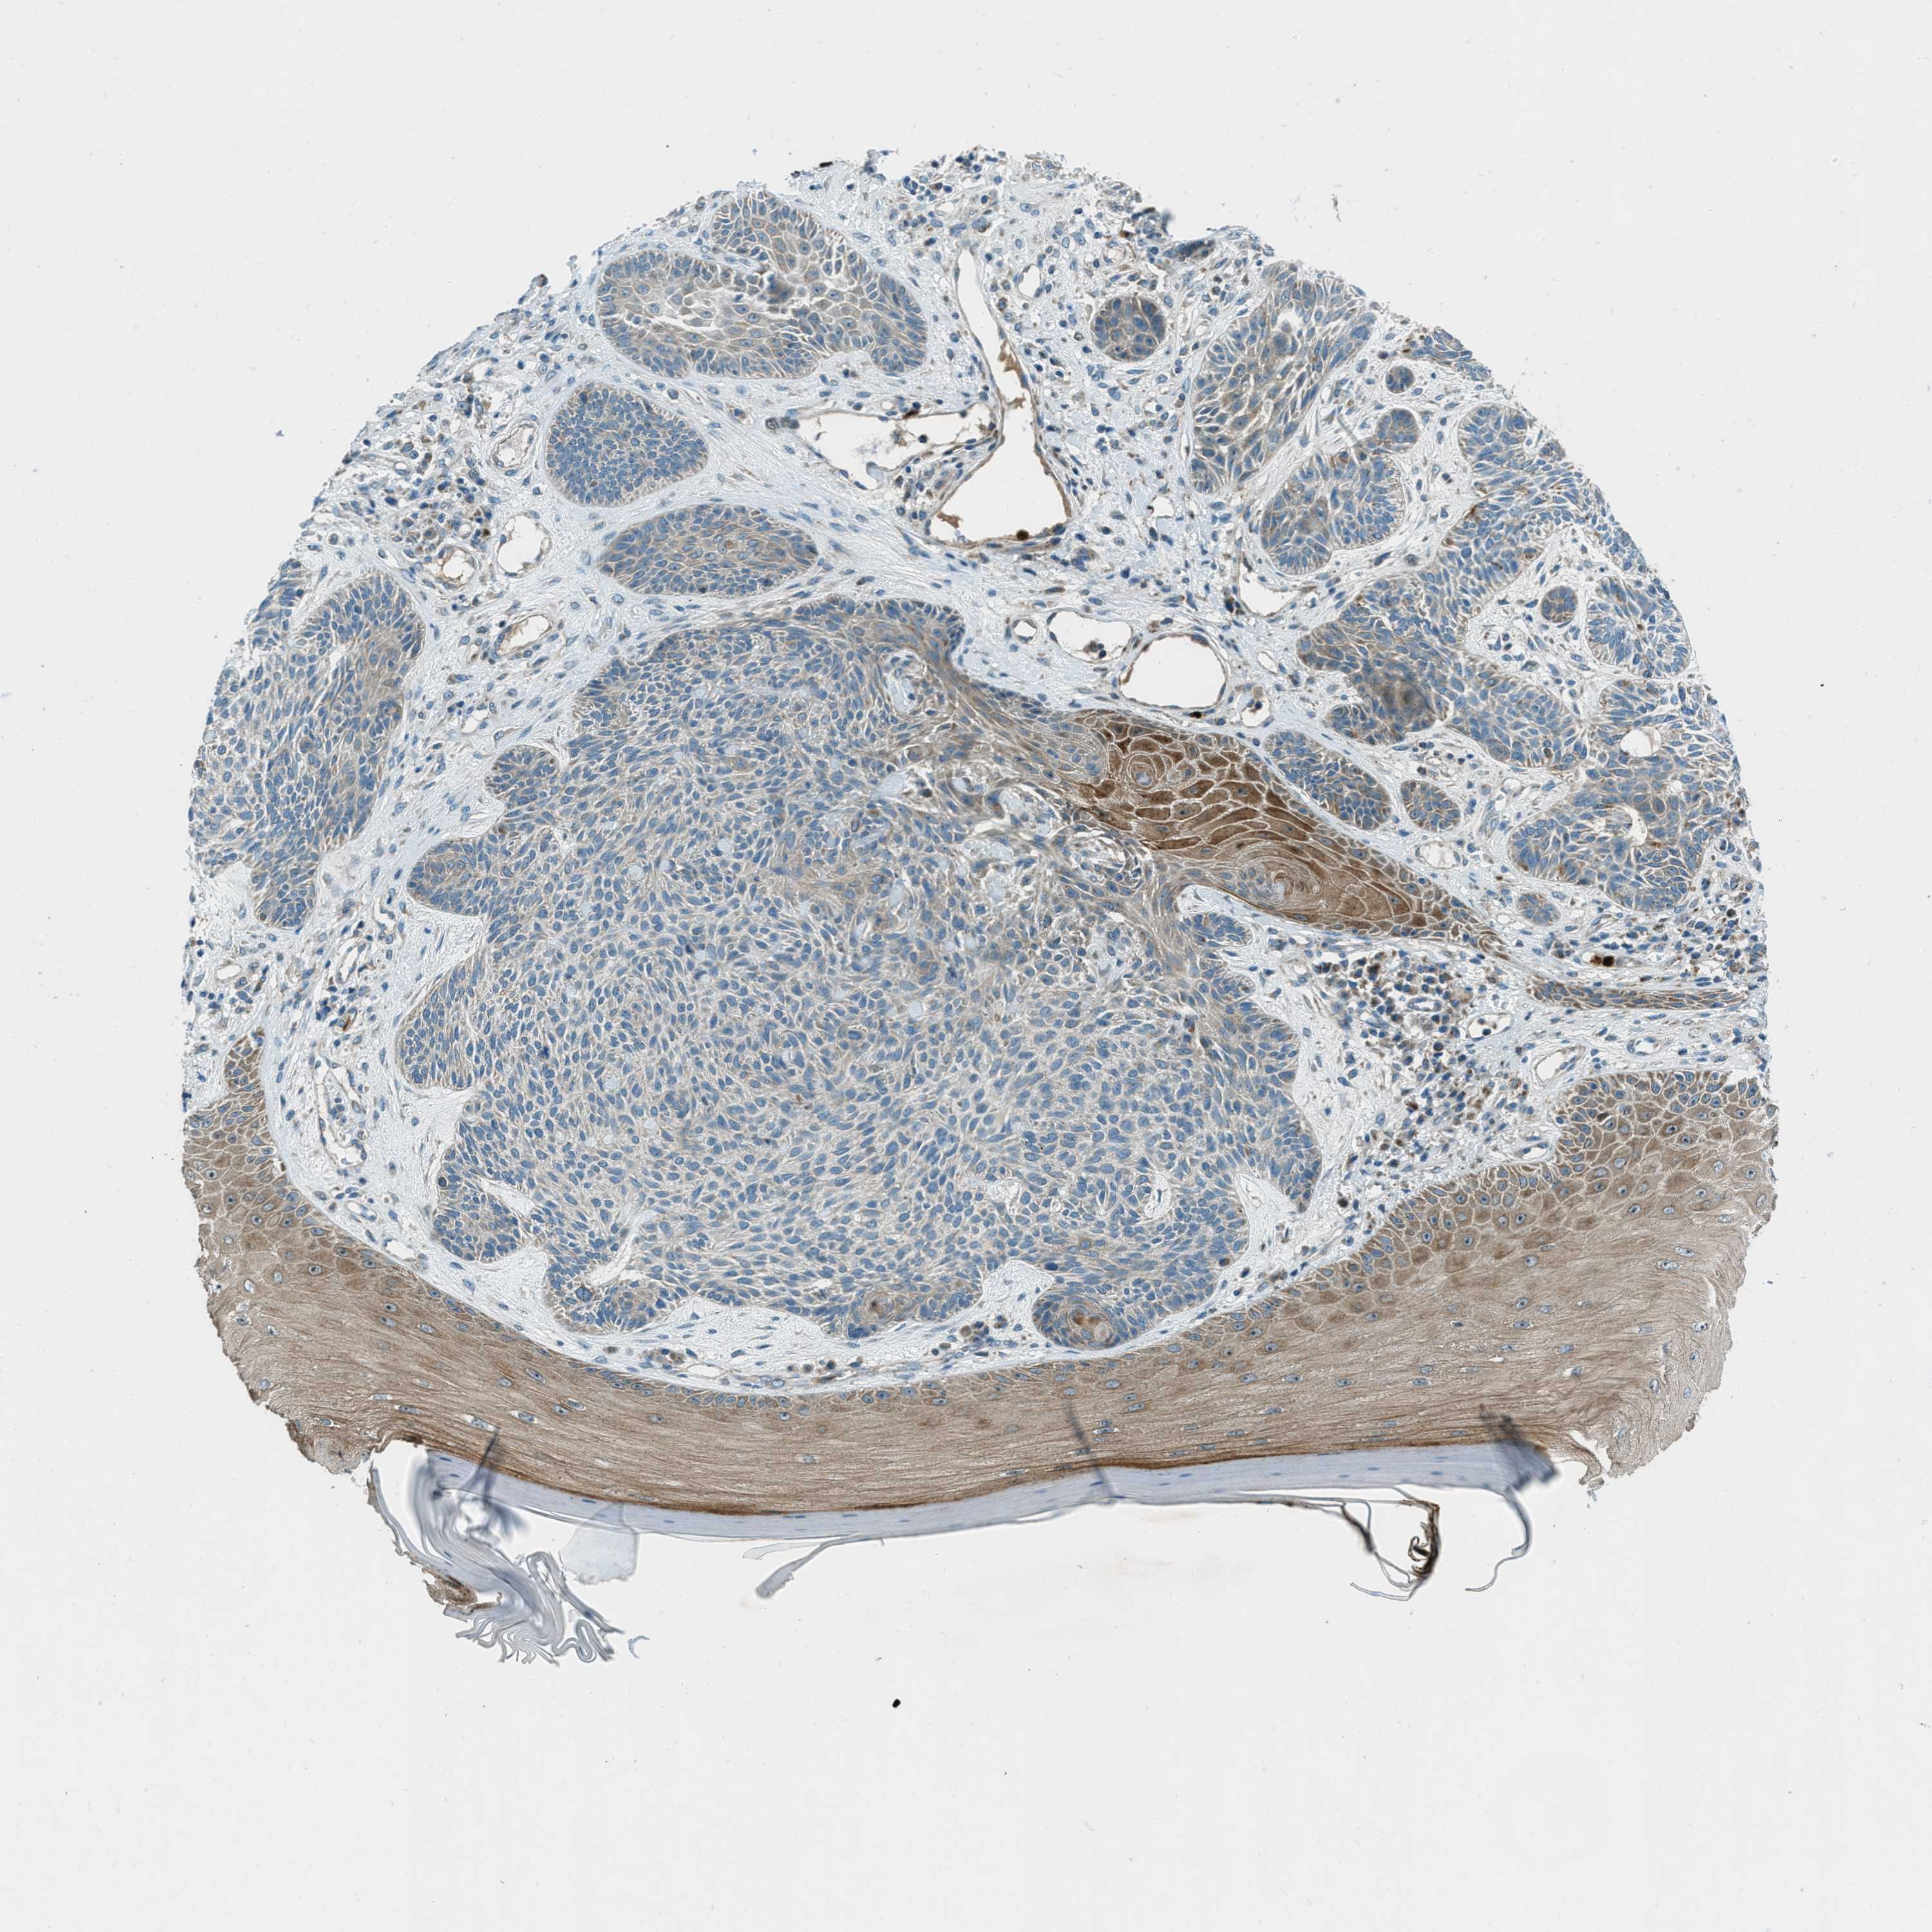

SKIN CANCER - Protein expressioni

A mouse-over function shows sample information and annotation data. Click on an image to view it in a full screen mode. Samples can be filtered based on level of antibody staining by selecting one or several of the following categories: high, medium, low and not detected. The assay and annotation is described here.

Each image is clickable and will lead to virtual microscopy that enables deeper exploration of all samples and also displays staining intensity scores, fraction scores and subcellular localization as well as patient and tissue information for each sample.

Antibody HPA017322

Staining

High

Intensity

Strong

Quantity

>75%

Location

Nuclear

Squamous cell carcinoma in situ, NOS

Squamous cell carcinoma, NOS

Squamous cell carcinoma, metastatic, NOS

Basal cell carcinoma